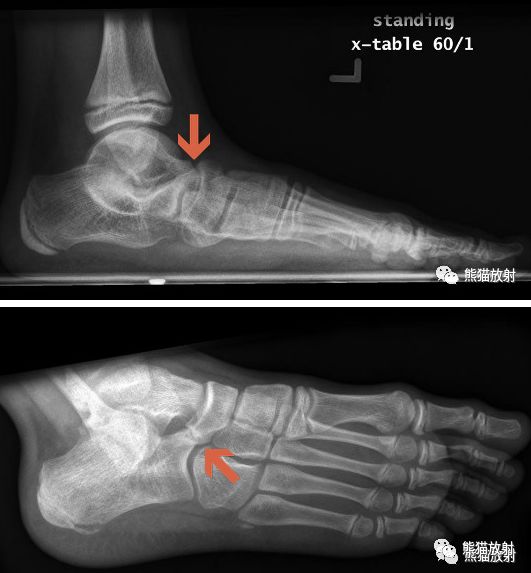

先看一个病例:患者,男性,16岁,足部疼痛。

足正侧位平片

食蚁兽鼻征

1、足侧位X线片上。

2、食蚁兽的鼻子:跟骨的前上部管状伸长,接近舟骨或与其重叠。

3、提示跟舟联合

跟舟联合在侧位X线片上呈现食蚁兽鼻征,拍摄45°内斜位X片观察跟舟联合